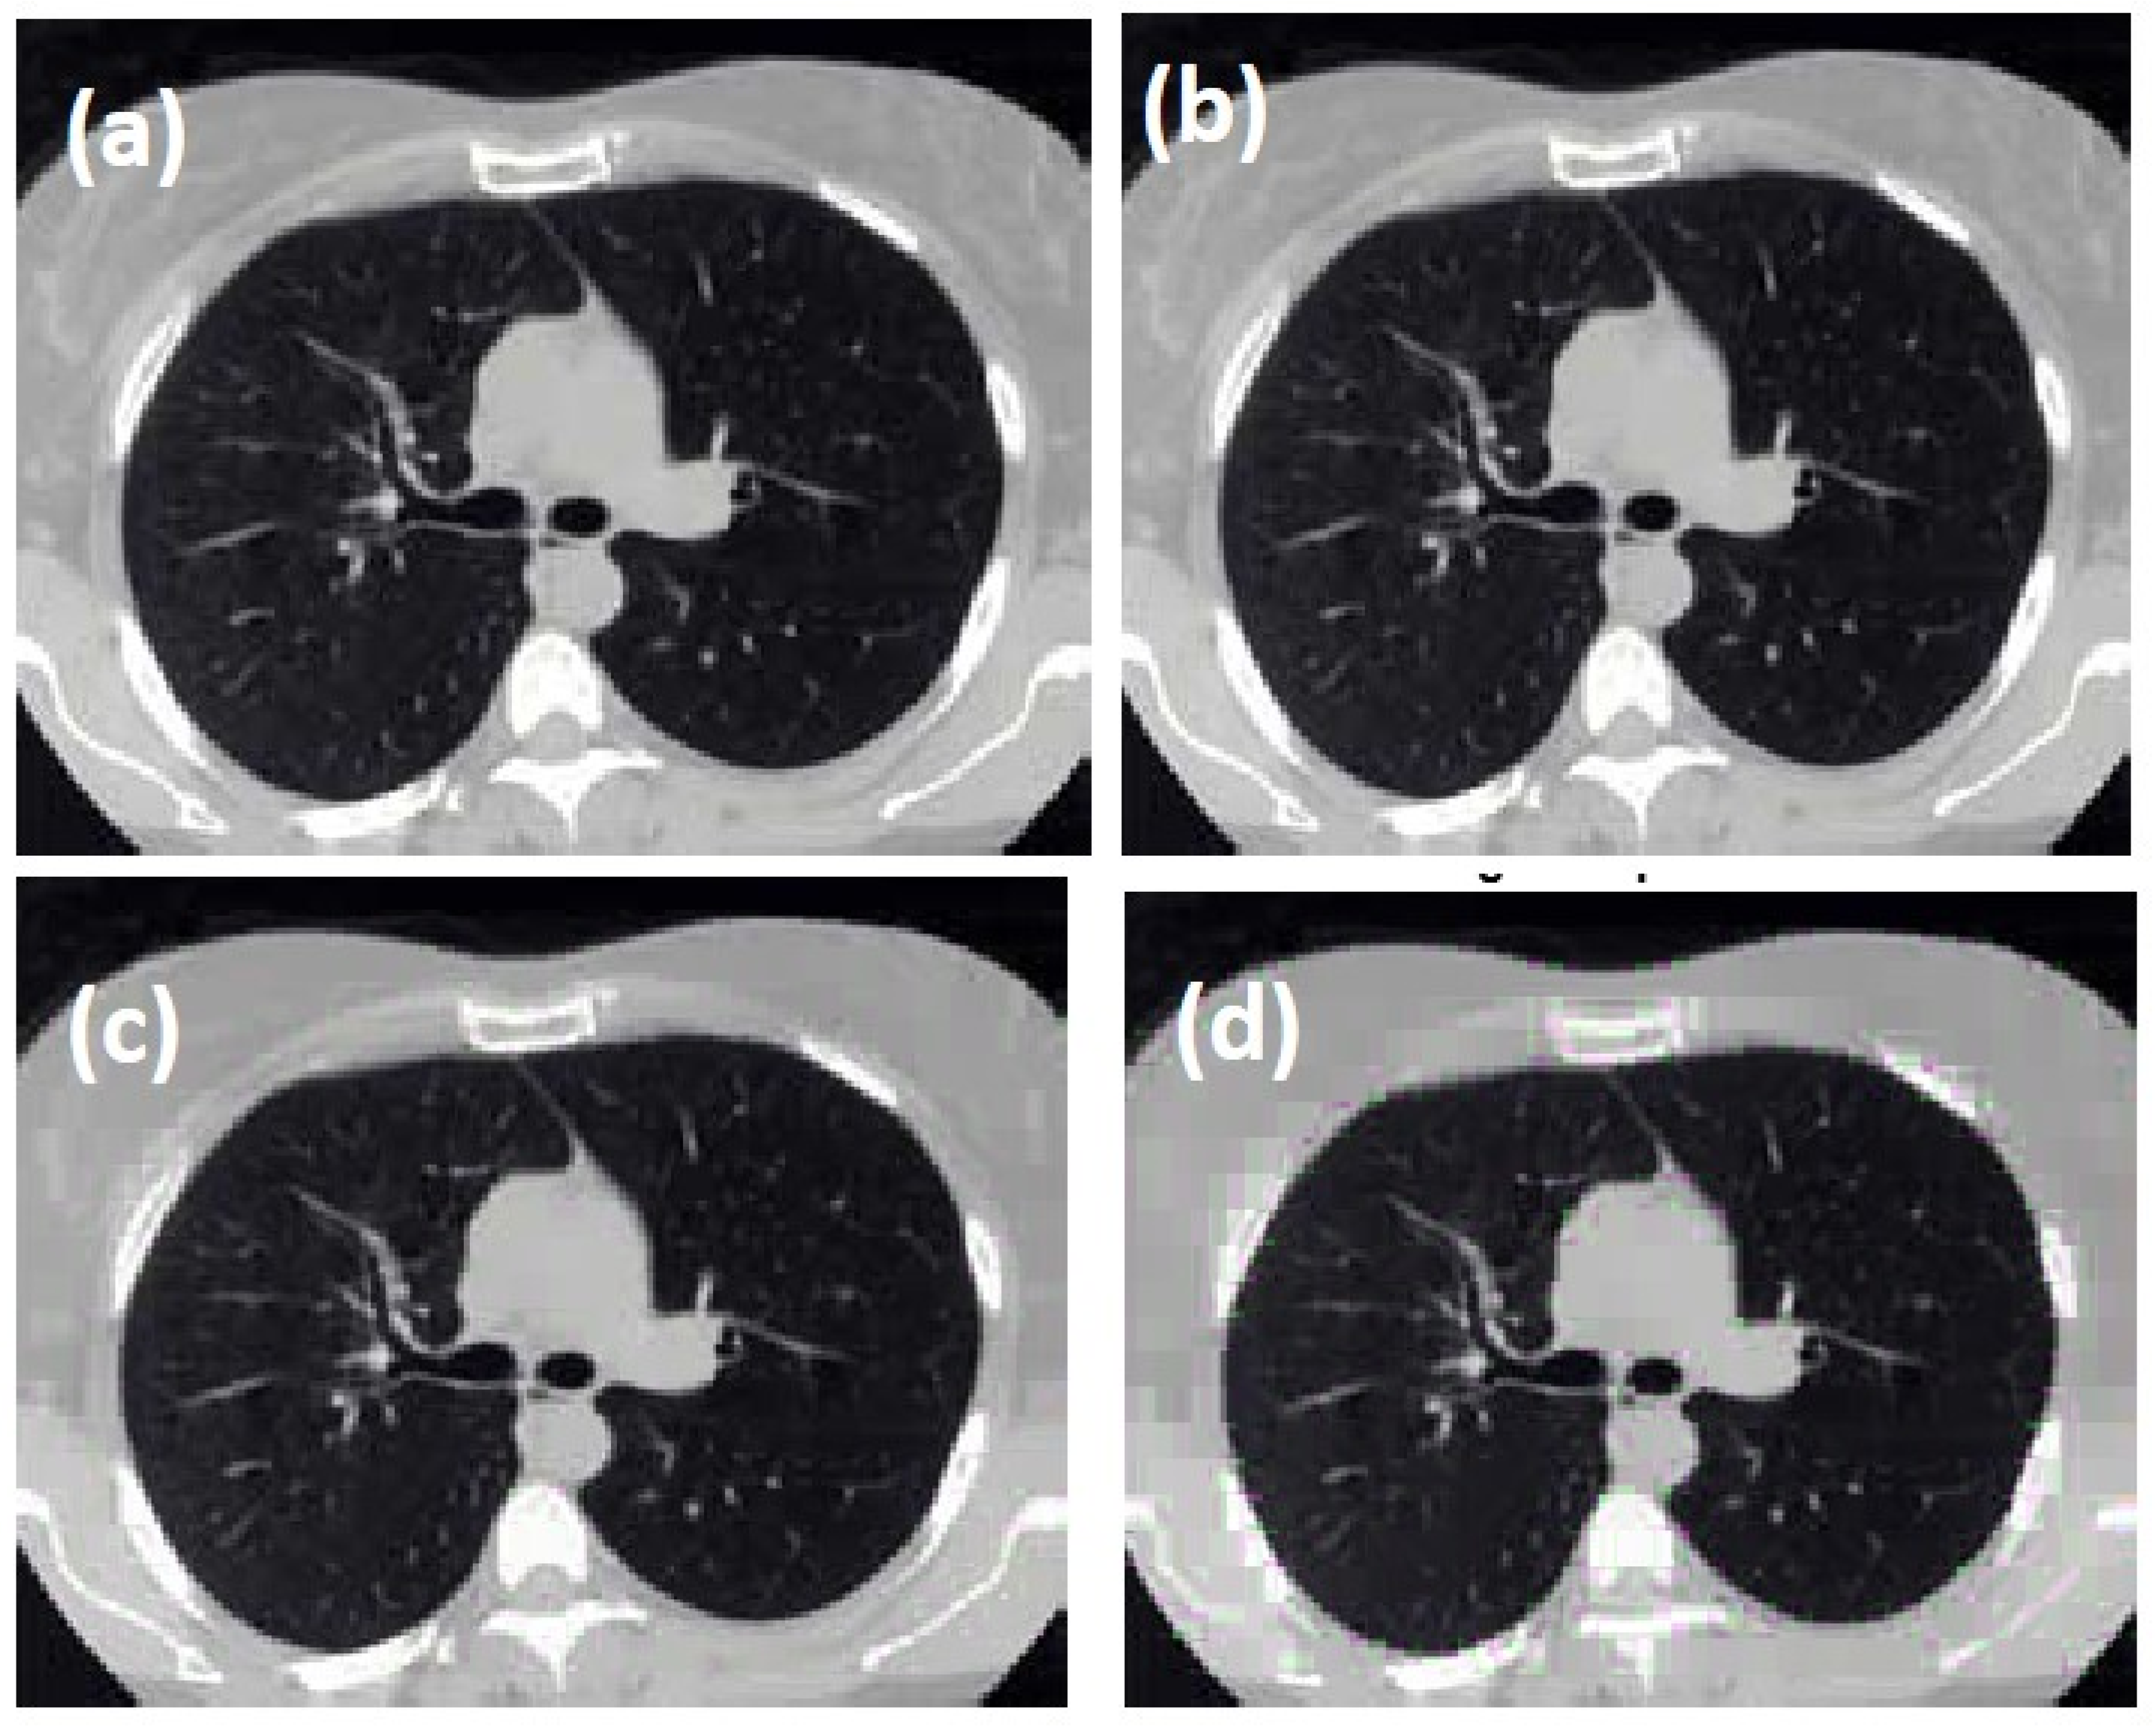

3.4. Medical Image Compression

In this article, a new high-speed DIT-FFT algorithm based on the radix-4 algorithm for medical image compression was proposed and simulated on a target device xc3s500e-5fg320. The simulation results show that radix-4 processes the input with less delay. From the time delay table, it is very clear that approximately 75% of the processing time is saved with less memory usage. The proposed radix algorithm also showed lower power consumption than the existing radix2, which allows the use of the present algorithm in the medical field, where low-power devices are preferable. This is another milestone for this article. Due to these advantages, the proposed algorithm is used in medical image compression. We observed different tolerances and their drop ratios. It is observed that the scaling factor for image compression depends on tolerance as directly proportional. According to the obtained results for different tolerances, such as 0.0007625, 0.003246, 0.013075 and 0.03924, the drop values are 0.10, 0.31, 0.61 and 0.83, respectively. The level of compression and tolerance values for medical images can be chosen based on the drop ratio and application. Before being taken for ASIC, it can be tested on FPGA for speed and further embedding of the required components.

Figure 25. Compressed image with (a) tolerance = 0.0007625 resulting in a drop ratio of 0.10.; (b) tolerance = 0.003246 resulting in drop ratio of 0.31; (c) tolerance = 0.013075 resulting in drop ratio of 0.61; (d) tolerance = 0.03924 resulting in a drop ratio of 0.83.